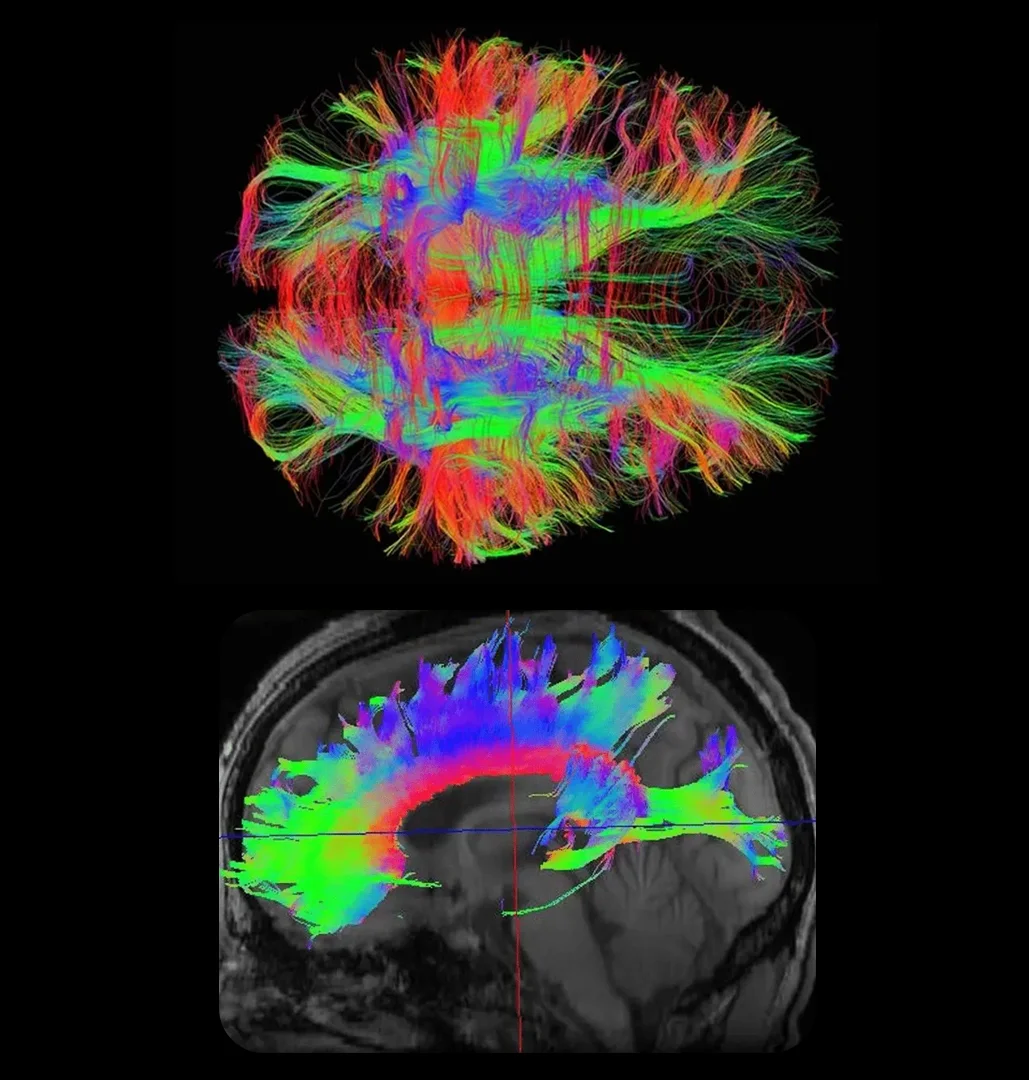

DIFFUSION TENSOR IMAGING (dti)

WHAT IS A DTI EXAM?

Diffusion Tensor Imaging (DTI) is one of the most advanced tools available for detecting traumatic brain injuries that traditional MRI and CT scans often overlook. By mapping white matter pathways, DTI uncovers diffuse axonal injury (DAI), even after mild trauma.

DTI delivers deeper brain visualization and objective evidence of injury, empowering earlier detection, clearer answers, and more confident clinical decisions.

WHY DTI STUDIES ARE IMPORTANT

Diffusion Tensor Imaging (DTI) is highlighted as a superior diagnostic tool for identifying brain issues that standard imaging might overlook.